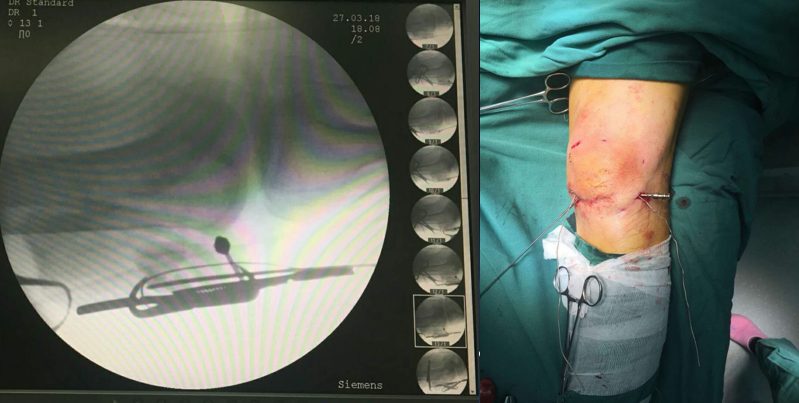

点氏复位钳经皮复位打入一克氏针临时固定

用电钻在髌骨上下极打一骨洞,用腰穿针带过钢丝

紧贴钢丝上方打入两髌骨针

折断髌骨针后再次收紧钢丝

术中照